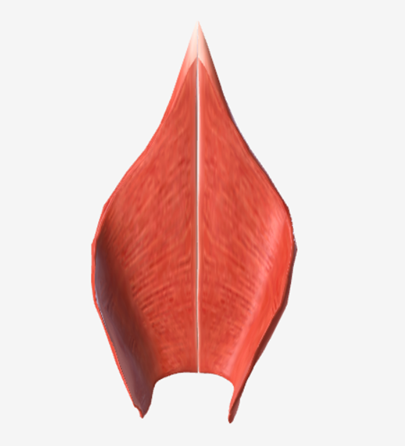

Inferior pharyngeal constrictor

origin is the oblique line of the thyroid laminae, coursing up and back to insert on the median pharyngeal raphe; function is to reduce the diameter of the lower pharynx